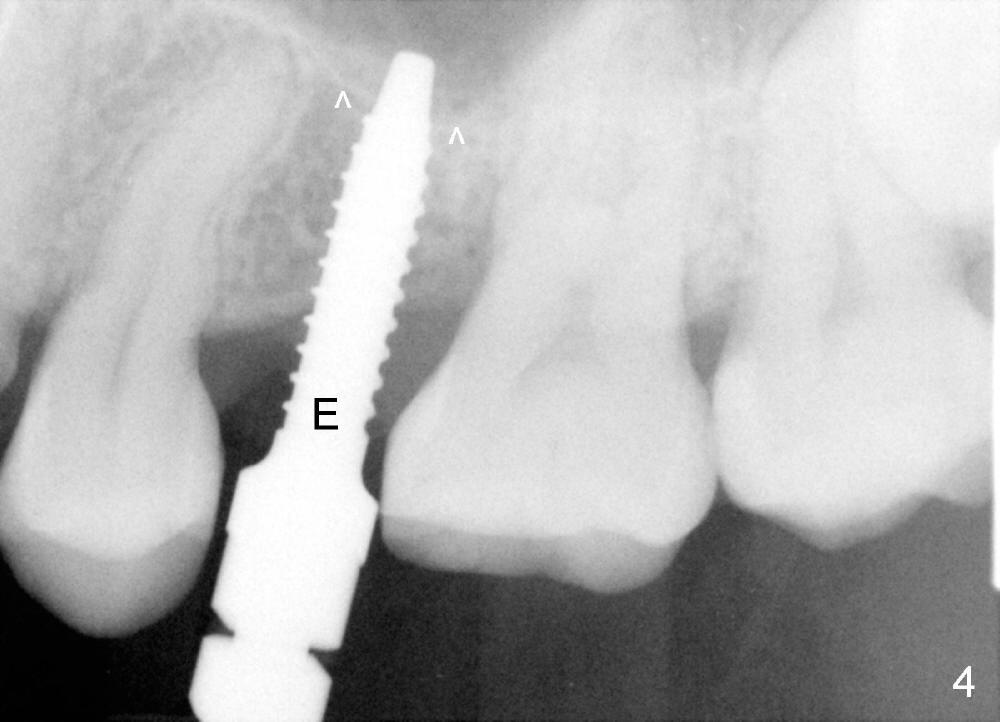

A 39-year-old lady is a dental phobic and finally agrees to restore long-termed missing upper left 2nd premolar (Fig.1). The adjoining teeth tilt toward the edentulous space. To place a 3.8x8 mm submerged implant (Fig.2, CBCT coronal section), enameloplasty is done (compare Fig.1 dashed lines with Fig.3 <). Since the density of the cancellous bone (<100 Hounsfield units (HU)) is much lower than that of the crest (300-400 HU) (Fig.2' <), osteotomy is initiated by 2 mm pilot drill (Fig.3 P) and finished by osteotomes (2 and 3 mm), bone expanders (2.6 mm (Fig.4) and 3.2 mm) and 3.8 mm tap drill. The implant is placed as planned with insertion torque around 35 Ncm (Fig.5). The implant is further lifted into the sinus by 1 mm without bone graft following the last X-ray. A healing abutment (4.1x3) is placed (Fig.6 <).

Limited orthodontic treatment is planned to close the diastema between the canine and the first premolar (Fig.1 ^) and to upright the molars, probably using osteointegrated implant as an anchorage.